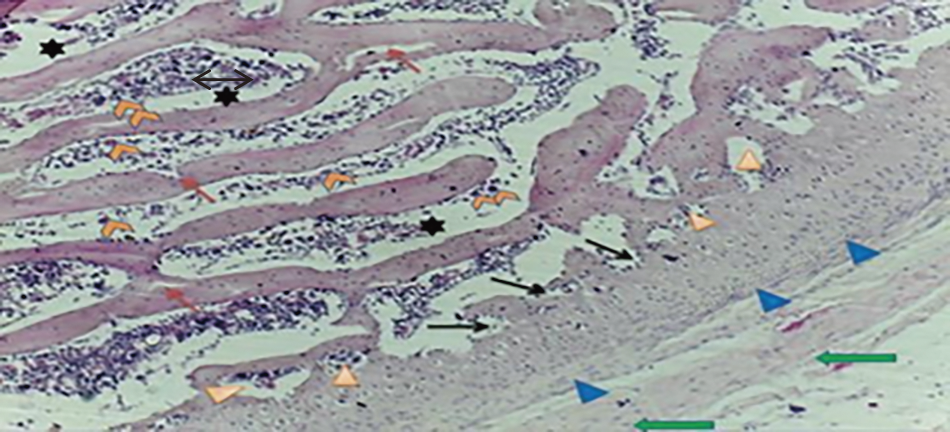

Results from papain injected knee joints revealed that an articular space was damaged, extensive degeneration, most chondrocytes lost the normal cellular morphology, narrowing the joint cavity between femoral condyles and tibial epiphyseal plate, rough surface, irregular discontinuity of superficial layer, condensation, proliferation of chondrocytes, cells death until the mid-zone of cartilage, moreover hypercellularity, disorientation of chondrocytes columns and formation of chondrocytes clusters (Fig. 11).

Fig. 11. Histological section of (OA) rat cartilage shows hypercellularity of surface layer (), proliferation of chondrocyte (), hypertrophied of synovial tissue (), discontinuous surface (), the epiphyseal plate () with irregular trabeculae (). (H & E) stain.

Sections from OA rats at tibia plateau region showed more fibrillation, shrunken chondrocytes with fragmented pyknotic nuclei, and extensive area of degenerated cartilage involving the entire zone of articular cartilage; the fibrillation and fissuring were noticed, and changes like denudation, erosion, and replacement by fibrous tissue were observed (Fig. 12). Moreover, the OA sections from patello femoral joint post 28 days showed underlying bone, increased of osteoclasts and osteoblast activity, alterations in the formation of bone and subchondral structure. This layer appeared with multinucleate cells and embedded within bone matrix, irregular collapse trabeculae, irregular osteoblasts, bone marrow cavity extensively infiltrated with osteoclast, abnormal cellularity, and partial replacement of bone marrow by fibrotic tissue (Figs. 13 and 14).

Fig 12. Section from (OA) rat at tibia plateau region showed moderate to severe synovitis (), discontinuity of synovium (), extensive chondrocytes degeneration (), foci of aggregated chondrocyte () noticed, expanded adipose tissue () with fibrous connective tissue (). (H & E) stain.